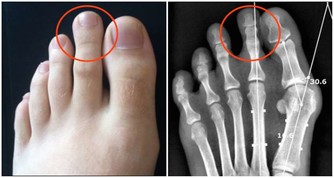

3、痔瘡和肛裂:如果患者長期便秘的話,則是會導致靜脈回流不暢,久而久之就會形成痔瘡,而如果糞便劃破肛門管的話,則是會形成肛裂。